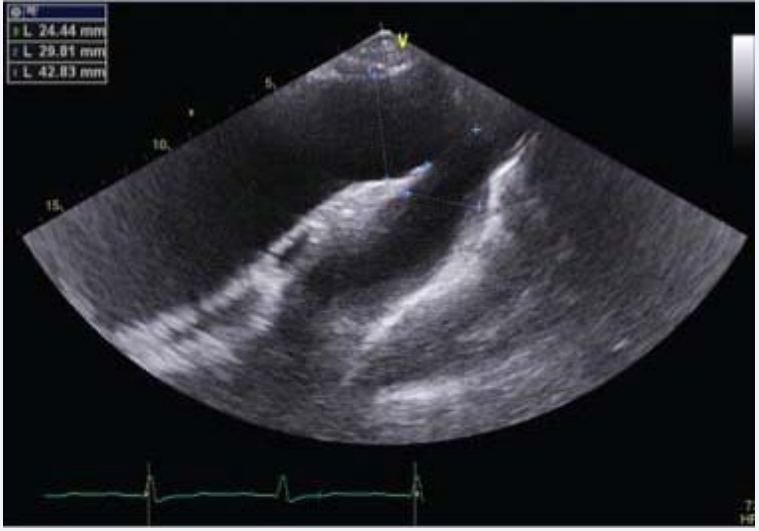

secondary to a large ascending aortic aneurysm (Figure 2d),

Transthoracic echocardiography – suprasternal view,  showing a dilation only of the ascending aorta.

Figure 2d: Transthoracic echocardiography – suprasternal view, showing a dilation only of the ascending aorta.

with the following 2D measures: aortic ring = 4.1 cm, Valsalva sinuses = 5.18 cm, sino-tubular junction = 7.1 cm and ascending aorta = 8.7 cm. The left ventricle was enlarged, with ejection fraction (calculated by Simpson’s method and using 3D software) of 41% and global longitudinal strain of -14.4% (Figure 3).